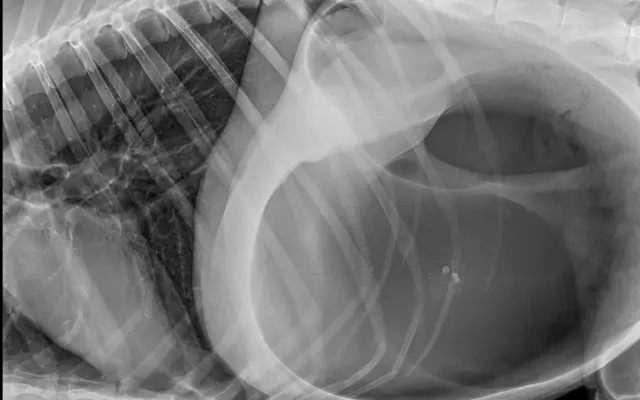

Fotogalerie